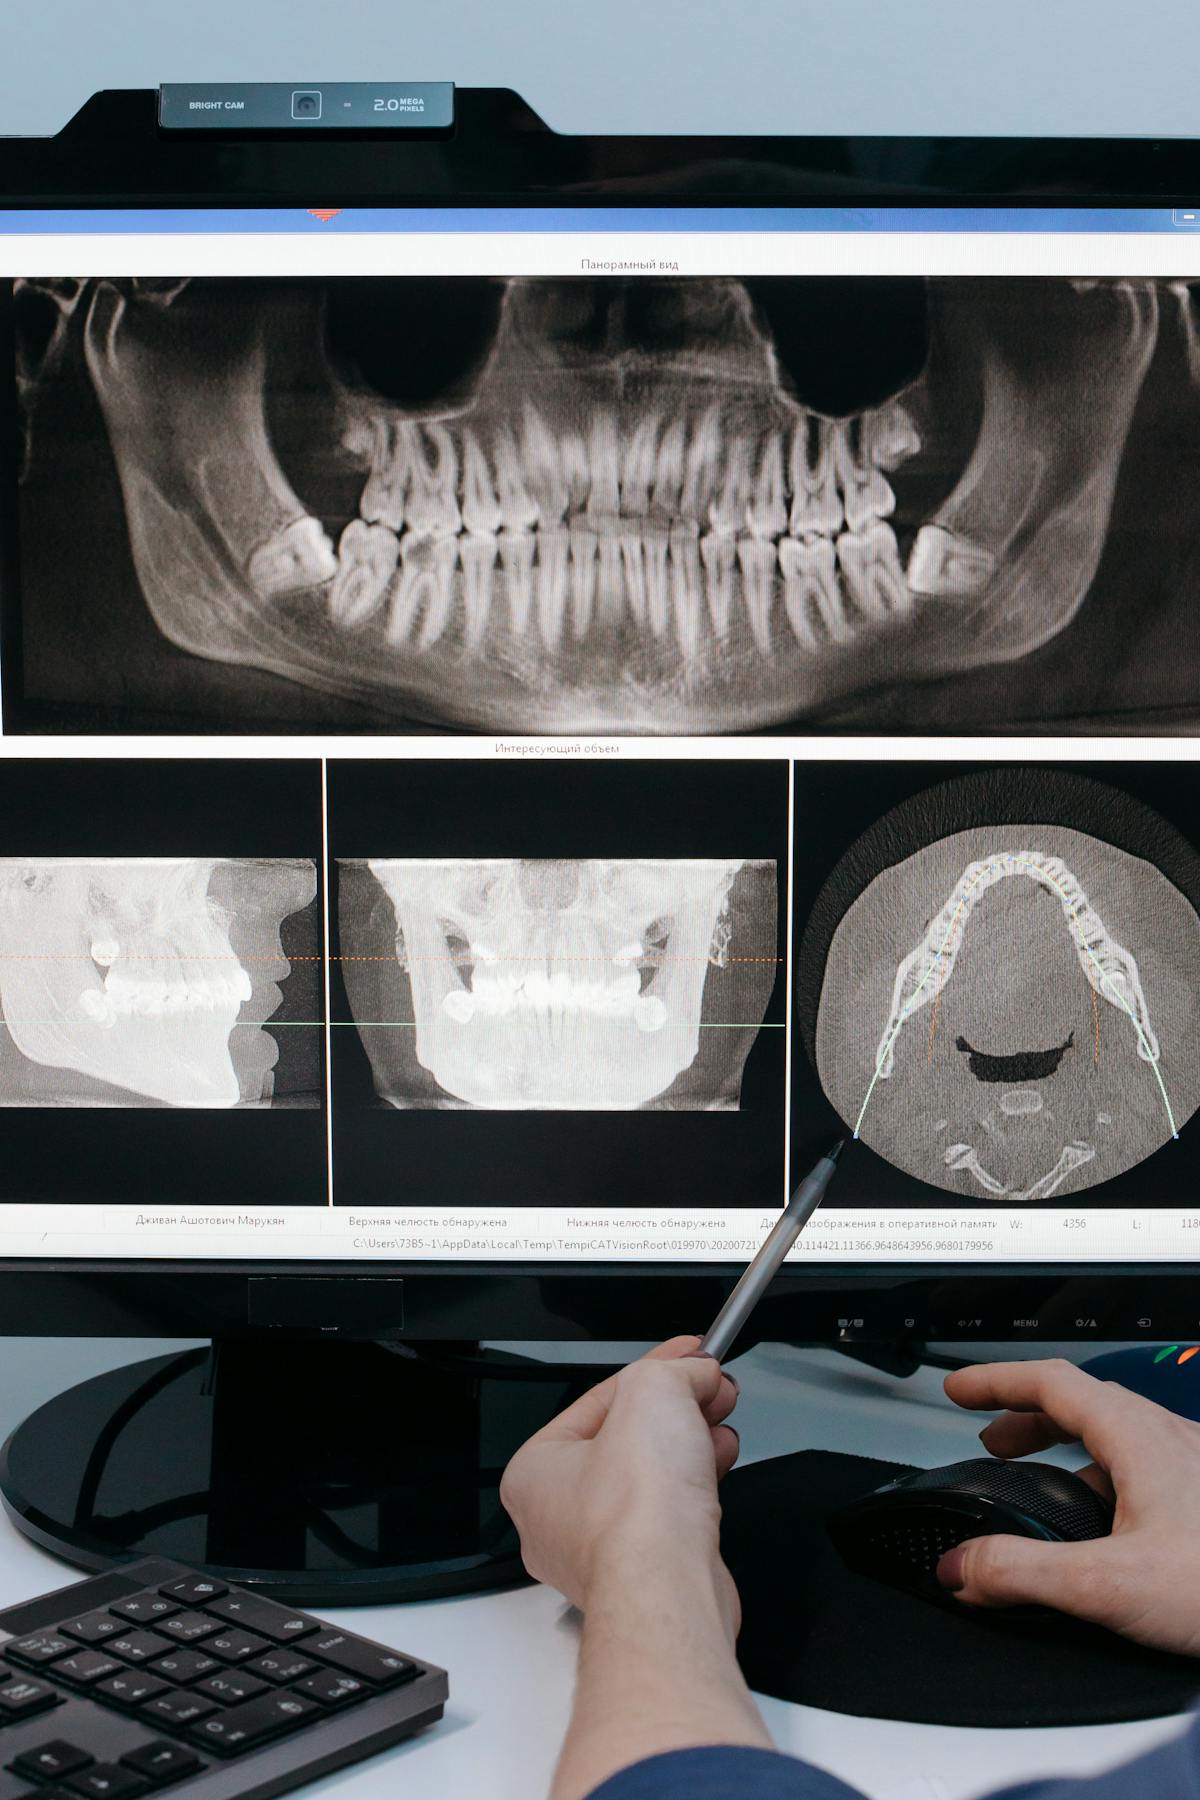

It starts with a thorough assessment. Your dentist needs to understand your bone density, gum health, and overall medical history before recommending anything. Not everyone is a candidate straight away, and an honest practitioner will tell you that upfront.

The implant itself is a small titanium post that gets placed into the jawbone. Over the next 3-6 months, something remarkable happens - the bone grows around and fuses with the titanium. This process, called osseointegration, is what gives implants their stability.